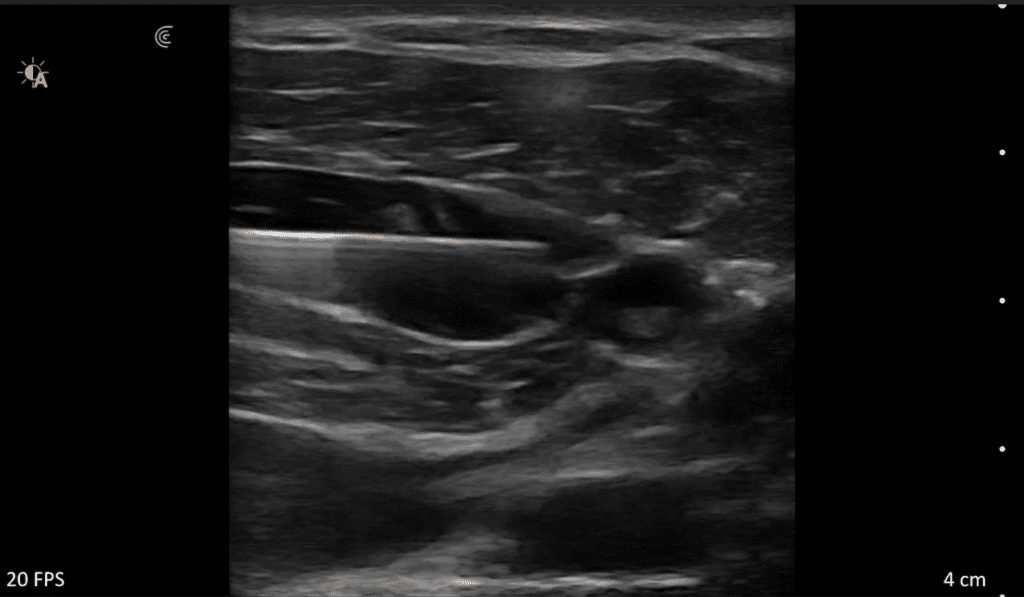

Clarius HD3 is the ideal wireless ultrasound scanner for musculoskeletal (MSK) imaging and procedural guidance. Make a confident diagnosis with high-resolution imaging of muscles, joints, ligaments, tendons, and cartilage both at rest and in motion.

What I like about Clarius is that it is an excellent ultrasound that allows me to have versatility, quality and precision.